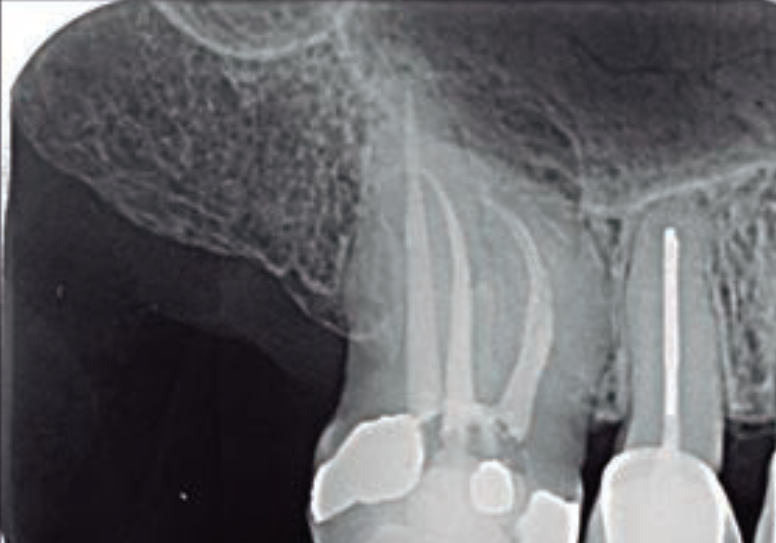

A radiografia periapical e, quando necessário, a tomografia computadorizada de feixe cônico (TCFC) são ferramentas indispensáveis para essa avaliação. A detecção precoce desses fatores pode alterar drasticamente o plano de tratamento e o prognóstico.

A profundidade da bolsa, a perda óssea radiográfica e o envolvimento de furca são cuidadosamente avaliados. Então, a presença de uma bolsa periodontal profunda e estreita, que se estende até o ápice, é um indicativo clássico de envolvimento endodôntico.